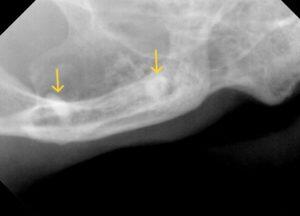

レントゲン検査では、

右上顎臼歯の残根2本と下顎臼歯の残根1本、犬歯は歯冠切除を実施していましたが歯肉に近い場所でした。